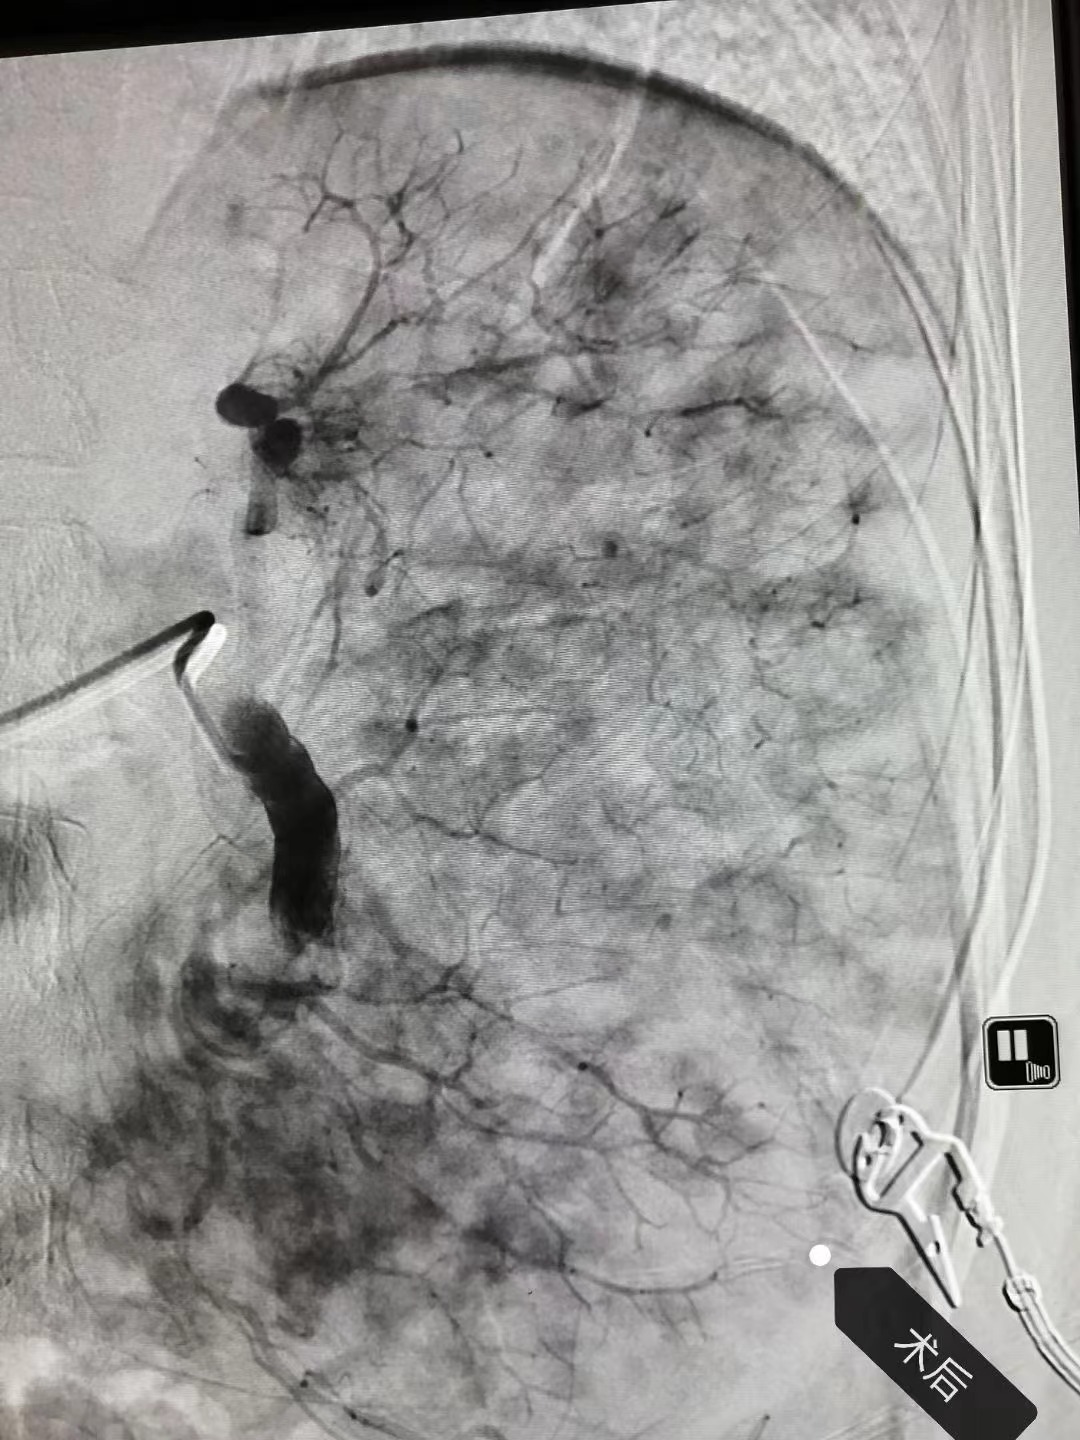

部分脾动脉栓塞术